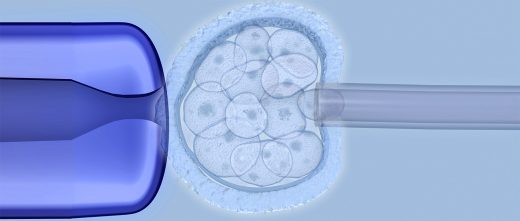

La conception du bébé-médicament est réalisée à travers les techniques de procréation assistée.

- On procède à la fécondation in vitro avec les ovocytes qui sont arrivés à maturation pendant la procédure précédente.